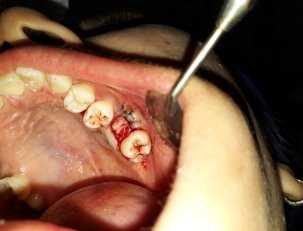

Дефект костной ткани 6 мм

Ушивание тканей над перфорацией

Клинический случай: Пац. А 18 лет. Амбулаторная история болезни № 13167. Обратилась день спустя после удаления 26 зуба. Анамнез: зуб был удален по поводу обострившегося хронического периодонтита. Жалобы: на хлюпанье — попадание воды в нос из полости рта, на боль пациент особо жалоб не предявила. Диагноз: перфорация верхнечелюстной пазухи в области 26 зуба. Методика оперативного вмешательства: под инфильтрационной анестезией (sol Articaini 1.5 мл — 2 %) промывали рану и лунку с антисептическим раствором содержащим метронидазол. (рис 1)

Техника пластики проводилась таким же путем как описано выше. (рис 2)